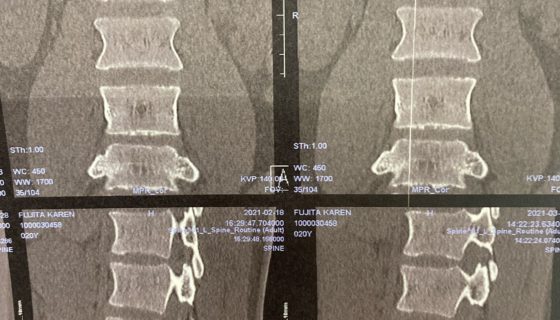

カテゴリー 日常 瑞穂 投稿者 作成者: Kiyoshi 投稿日 2021/03/18 瑞穂 へのコメントはまだありません 今日も10年ぶりくらいの工場。 満開の菜の花。 今日はどこも大渋滞で動かない。 花壇に猫が入るから急ぎで柵作り。 ネモフィラが大きくなるまで仕方ない。 華恋はJISSの病院。 大渋滞で遅くなった。 骨は順調だけどあとひと月。 ← 古河 → 光ヶ丘 コメントを残すメールアドレスが公開されることはありません。 * が付いている欄は必須項目ですコメント * 名前 * メール * サイト